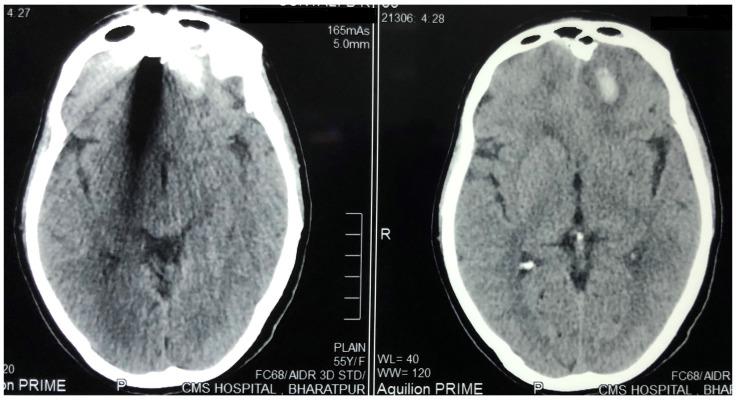

There are a number of ways in which one can sustain a head injury. Even if you are doing simple household activities or going out for a morning walk, you cannot be sure of what type of injury awaits you. The source of injury may be a pressure cooker whistle acting as a projectile or a hailstone falling from the sky. Such injuries are common in Nepal, considering the socio-demographic and geographic conditions. In this article, we present two such very rare cases of head injury. The first case is a middle-aged woman who sustained an accidental injury to the face associated with fracture of frontal sinus and frontal contusion, following the impact from a high momentum projectile in the form of the pressure regulator of a pressure cooker. She underwent craniotomy and removal of the foreign body. In the second case, an elderly man sustained minor injury to the head following the fall of hail. The abrasions and contusions produced by the hail were managed conservatively. Since he did not have any clinical evidence of head injury, other than multiple abrasions with contusions in the scalp, he did not undergo any imaging studies. He did not have any neurological deficits. The postoperative period was uneventful for the first patient and she was followed up for one month. The second patient was lost to follow-up. Successful management of two very rare cases of head injuries from Nepal are reported. Proper care and maintenance of the house-hold utensils that are constantly used may protect people from head injuries. Though natural calamities cannot always be avoided, simple measures like using an umbrella while going outdoors may protect individuals from head injuries due to hailstones.

有许多种方式可能导致头部受伤。即使你只是在做简单的家务或晨练,也无法确定会遭遇哪种类型的伤害。伤害可能来自高压锅的哨子,它可能成为一个抛射物,也可能是天降的冰雹。在尼泊尔,由于社会人口统计学和地理条件的影响,这类伤害很常见。在本文中,我们介绍了两例非常罕见的头部受伤病例。第一例是一名中年女性,她在面部意外受伤,伴有额窦和额部挫伤,受伤原因是高压锅的压力调节阀以高动量抛射物的形式撞击。她接受了开颅手术和异物取出术。第二例是一名老年男性,他在被冰雹砸伤后头部受轻伤。对冰雹造成的擦伤和挫伤进行了保守治疗。由于除了头皮多处擦伤和挫伤外,他没有任何头部受伤的临床证据,因此没有进行任何影像学检查。他没有任何神经功能缺损。第一例患者的术后恢复顺利,随访一个月。第二例患者失访。本文报告了两例来自尼泊尔的非常罕见的头部受伤病例的成功治疗。对经常使用的家用器具进行适当的维护和保养,可能有助于防止头部受伤。虽然自然灾害无法完全避免,但像在户外时使用雨伞这样简单的措施,可能有助于防止因冰雹导致的头部受伤。